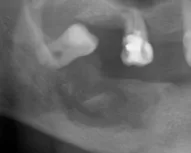

Un paciente de 35 años con antecedentes de diabetes tipo II mal controlada se presenta con dolor en su mandíbula y fiebre. Tiene una úlcera en la encía que no ha cicatrizado en varios meses. producto de una extraccion Las imágenes muestran los siguientes signos.

maxilar inferior de aproximadamente 3 cm se evidencia pequeños secuestros óseos y destrucción amplia esta imagen es compatible con una osteomilitis

imagen radiolucida en el maxilar inferior de aproximadamente 3 cm se evidencia pequeños secuestros óseos y destrucción amplia esta imagen es compatible con una osteomilitis